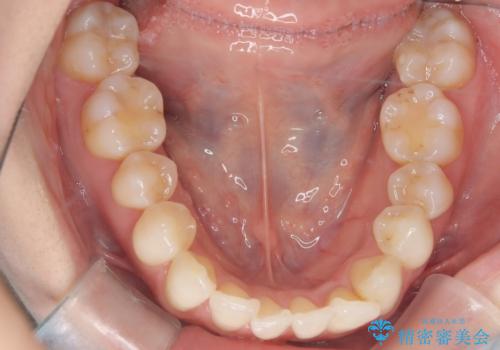

矯正後の後戻りで前歯にガタツキができてしまった インビザラインで改善

- 子どものときにワイヤー矯正をしていたが、後戻りによって前歯のガタツキが気になってきたとのことで来院されました。

アライナー矯正希望だったため、インビザラインによる治療を行いました。